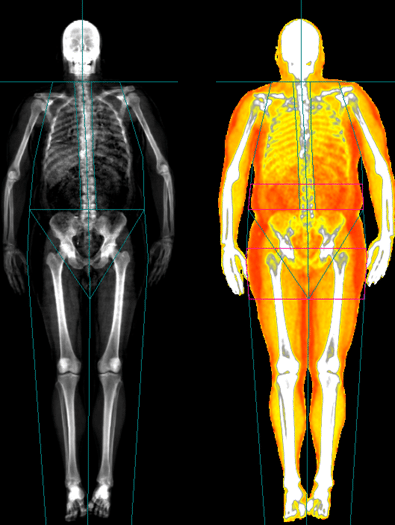

Late-stage trials and body-composition scans (DXA) show that while all three medications can cause major weight loss, what that weight is made of matters.4–6,10

- CagriSema stands out because people tend to lose more fat and less muscle, relative to total weight lost.3,10

- Body-scan (DXA) data show a higher proportion of lean mass remaining after weight loss.3,10